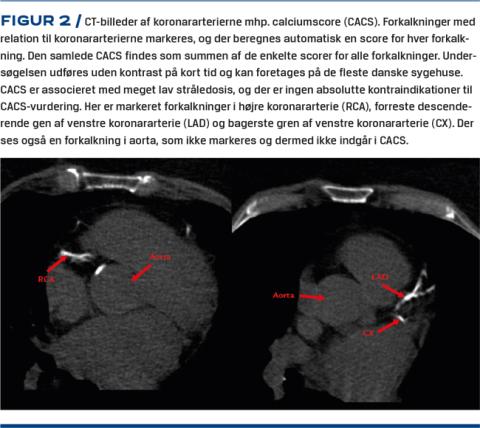

Indholdet af kalk i koronararterierne kan bestemmes ved CACS vha. CT uden kontrast (Figur 2). CACS er associeret med mortalitet [18] og risiko for alvorlige kardiovaskulære hændelser [19] uafhængigt af risikofaktorer. Dette er også påvist hos asymptomatiske personer i et studie med 15 års followup [18] såvel som ved kortere followup [20]. Den samlede koronare kalkmængde, som er relateret til risikoen for fremtidige kardiovaskulære events kan på baggrund af CACS inddeles i meget lav (CACS = 0), lav (CACS = 1-10), moderat (CACS = 11-100), høj (CACS = 101-400) og meget høj (CACS > 400). Foruden en absolut score findes der percentiler for CACS, hvor man tager højde for køn, alder og etnicitet [21].

Billede